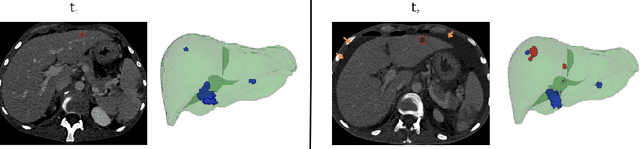

Abstract:Assessing cancer progression in liver CT scans is a clinical challenge, requiring a comparison of scans at different times for the same patient. Practitioners must identify existing tumors, compare them with prior exams, identify new tumors, and evaluate overall disease evolution. This process is particularly complex in liver examinations due to misalignment between exams caused by several factors. Indeed, longitudinal liver examinations can undergo different non-pathological and pathological changes due to non-rigid deformations, the appearance or disappearance of pathologies, and other variations. In such cases, existing registration approaches, mainly based on intrinsic features may distort tumor regions, biasing the tumor progress evaluation step and the corresponding diagnosis. This work proposes a registration method based only on geometrical and anatomical information from liver segmentation, aimed at aligning longitudinal liver images for aided diagnosis. The proposed method is trained and tested on longitudinal liver CT scans, with 317 patients for training and 53 for testing. Our experimental results support our claims by showing that our method is better than other registration techniques by providing a smoother deformation while preserving the tumor burden (total volume of tissues considered as tumor) within the volume. Qualitative results emphasize the importance of smooth deformations in preserving tumor appearance.